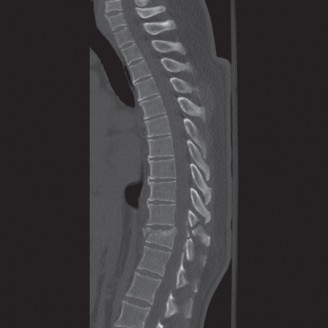

When surgical intervention becomes unavoidable, meticulous pre-operative planning is the cornerstone of a successful outcome. Advanced imaging is non-negotiable. An MRI with and without gadolinium contrast is the gold standard for defining the extent of the epidural abscess, the degree of neural compression, and the involvement of adjacent paraspinal musculature (e.g., psoas abscess). T1-weighted images typically show hypointense signals in the infected marrow, while T2-weighted and STIR sequences reveal hyperintense fluid and edema in the disc space and vertebral bodies. Gadolinium enhancement highlights the vascularized inflammatory phlegmon and the capsule of any abscesses.

In addition to MRI, a fine-cut computed tomography (CT) scan is essential for evaluating bony destruction. CT allows the surgeon to assess bone stock for pedicle screw purchase and to template the size of the interbody cages required for anterior column reconstruction. Upright standing radiographs (if the patient can tolerate them) or full-length supine films are necessary to evaluate global spinal alignment and regional kyphosis.